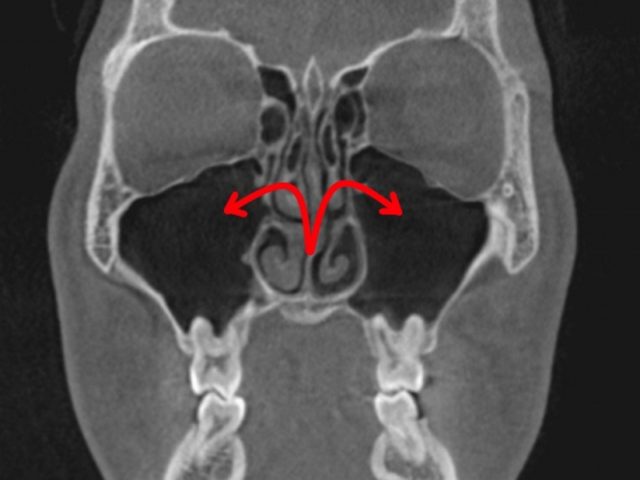

顔が痛い 頬骨も痛い とき 耳鼻科治療 上顎洞正面観自然孔 正面観

上は、上顎洞 自然孔という

上顎洞と、鼻腔との、

交通部分です。

通常、

上顎洞の膿は、

上顎洞粘膜の繊毛により、

自然孔(赤矢印)から排出されます。